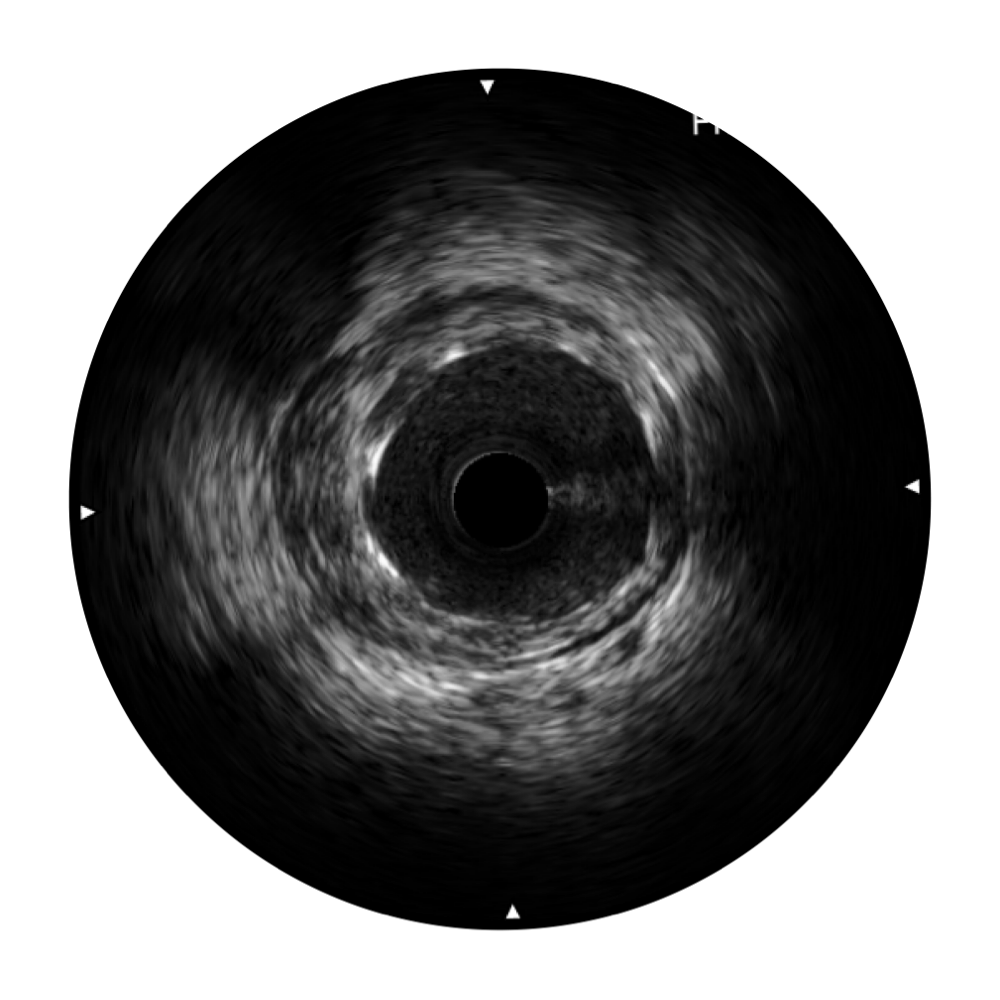

血管内超声(IVUS) 通过对病变程度、性质和累及范围的精确判断,可帮助选择治疗策略和方法,指导介入治疗过程,能够降低主要不良心血管事件,改善预后,在复杂病变介入治疗中用于指导支架置入的优势更为明显。血管内超声(IVUS)已成为精准心血管介入治疗的“金标准”。

db真人体育官网超宽频成像技术覆盖20-80MHz1或20-90MHz2频率范围, 提供优异的分辨力同时也保证充足的穿透深度

对比传统IVUS导管成像,db真人体育官网宽频IVUS图像的近场支架梁显影更细腻,远场中膜外血管仍清晰可辨,兼顾远中近,兼顾分辨力与穿透深度